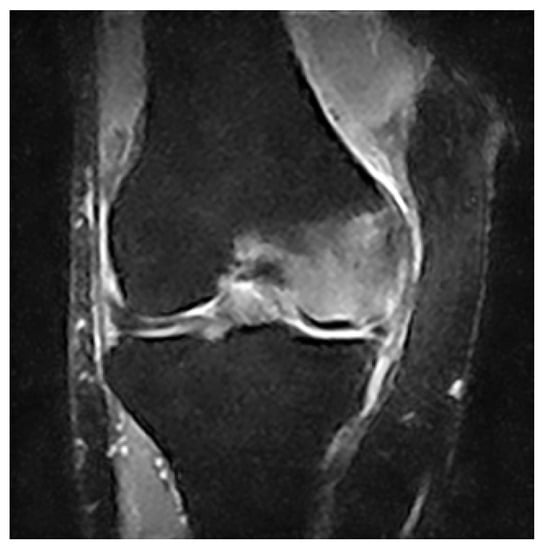

The archives of our institution were mined for the records of patients who had been diagnosed with primary BME of the knee from 1 January 2015 to 31 August 2021. The diagnosis was based on the sudden onset of acute non-traumatic knee pain and on abnormal bone marrow signal strength on MRI, specifically decreased bone marrow signal intensity on T1-weighted images and increased signal intensity on T2-weighted images, as presented in Figure 1.

Figure 1.

Coronal MRI image showing a typical BME pattern of our patients.